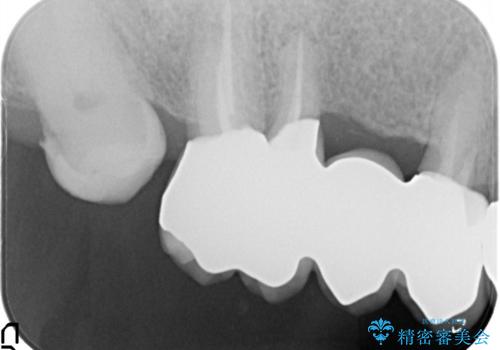

- 奥歯がなくて咬めないのと、全体的に見た目をよくしたいとのことで来院されました。

下顎の両側の奥歯が欠損しており、入れ歯をお持ちでしたが、うまく咬めずにほとんど使用していない状態でした。

上顎は全体的にクラウンの入れ替えと、下顎はインプラントの提案もしましたが、希望されなかったのでノンクラスプデンチャーの製作をする治療計画としました。

奥歯が欠損しており、上下の前歯が強く咬合する可能性があったので、上顎前歯の裏側は金属のものにしました。

お忙しい方でしたので、治療が終了するまでにじかんがかかってしまいましたが、奥歯でもしっかり咬めるようになったと喜んでいただけました。